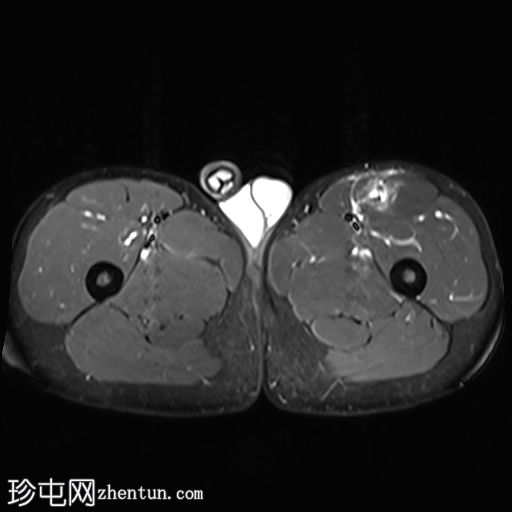

轴位

T1加权像

左侧股直肌近端肌腱交界处可见异常高信号,向远端延伸约至肌长一半。

可见清晰的充满液体的分离平面,呈“靶心征”,将双羽状间接头与浅表单羽状直接头分隔开,呈现出股直肌脱套样损伤的特征性影像

间接头肌纤维与近端肌腱保持连续,未见肌腱断裂或明显回缩。

可见轻度肌间及筋膜周围水肿。病例讨论